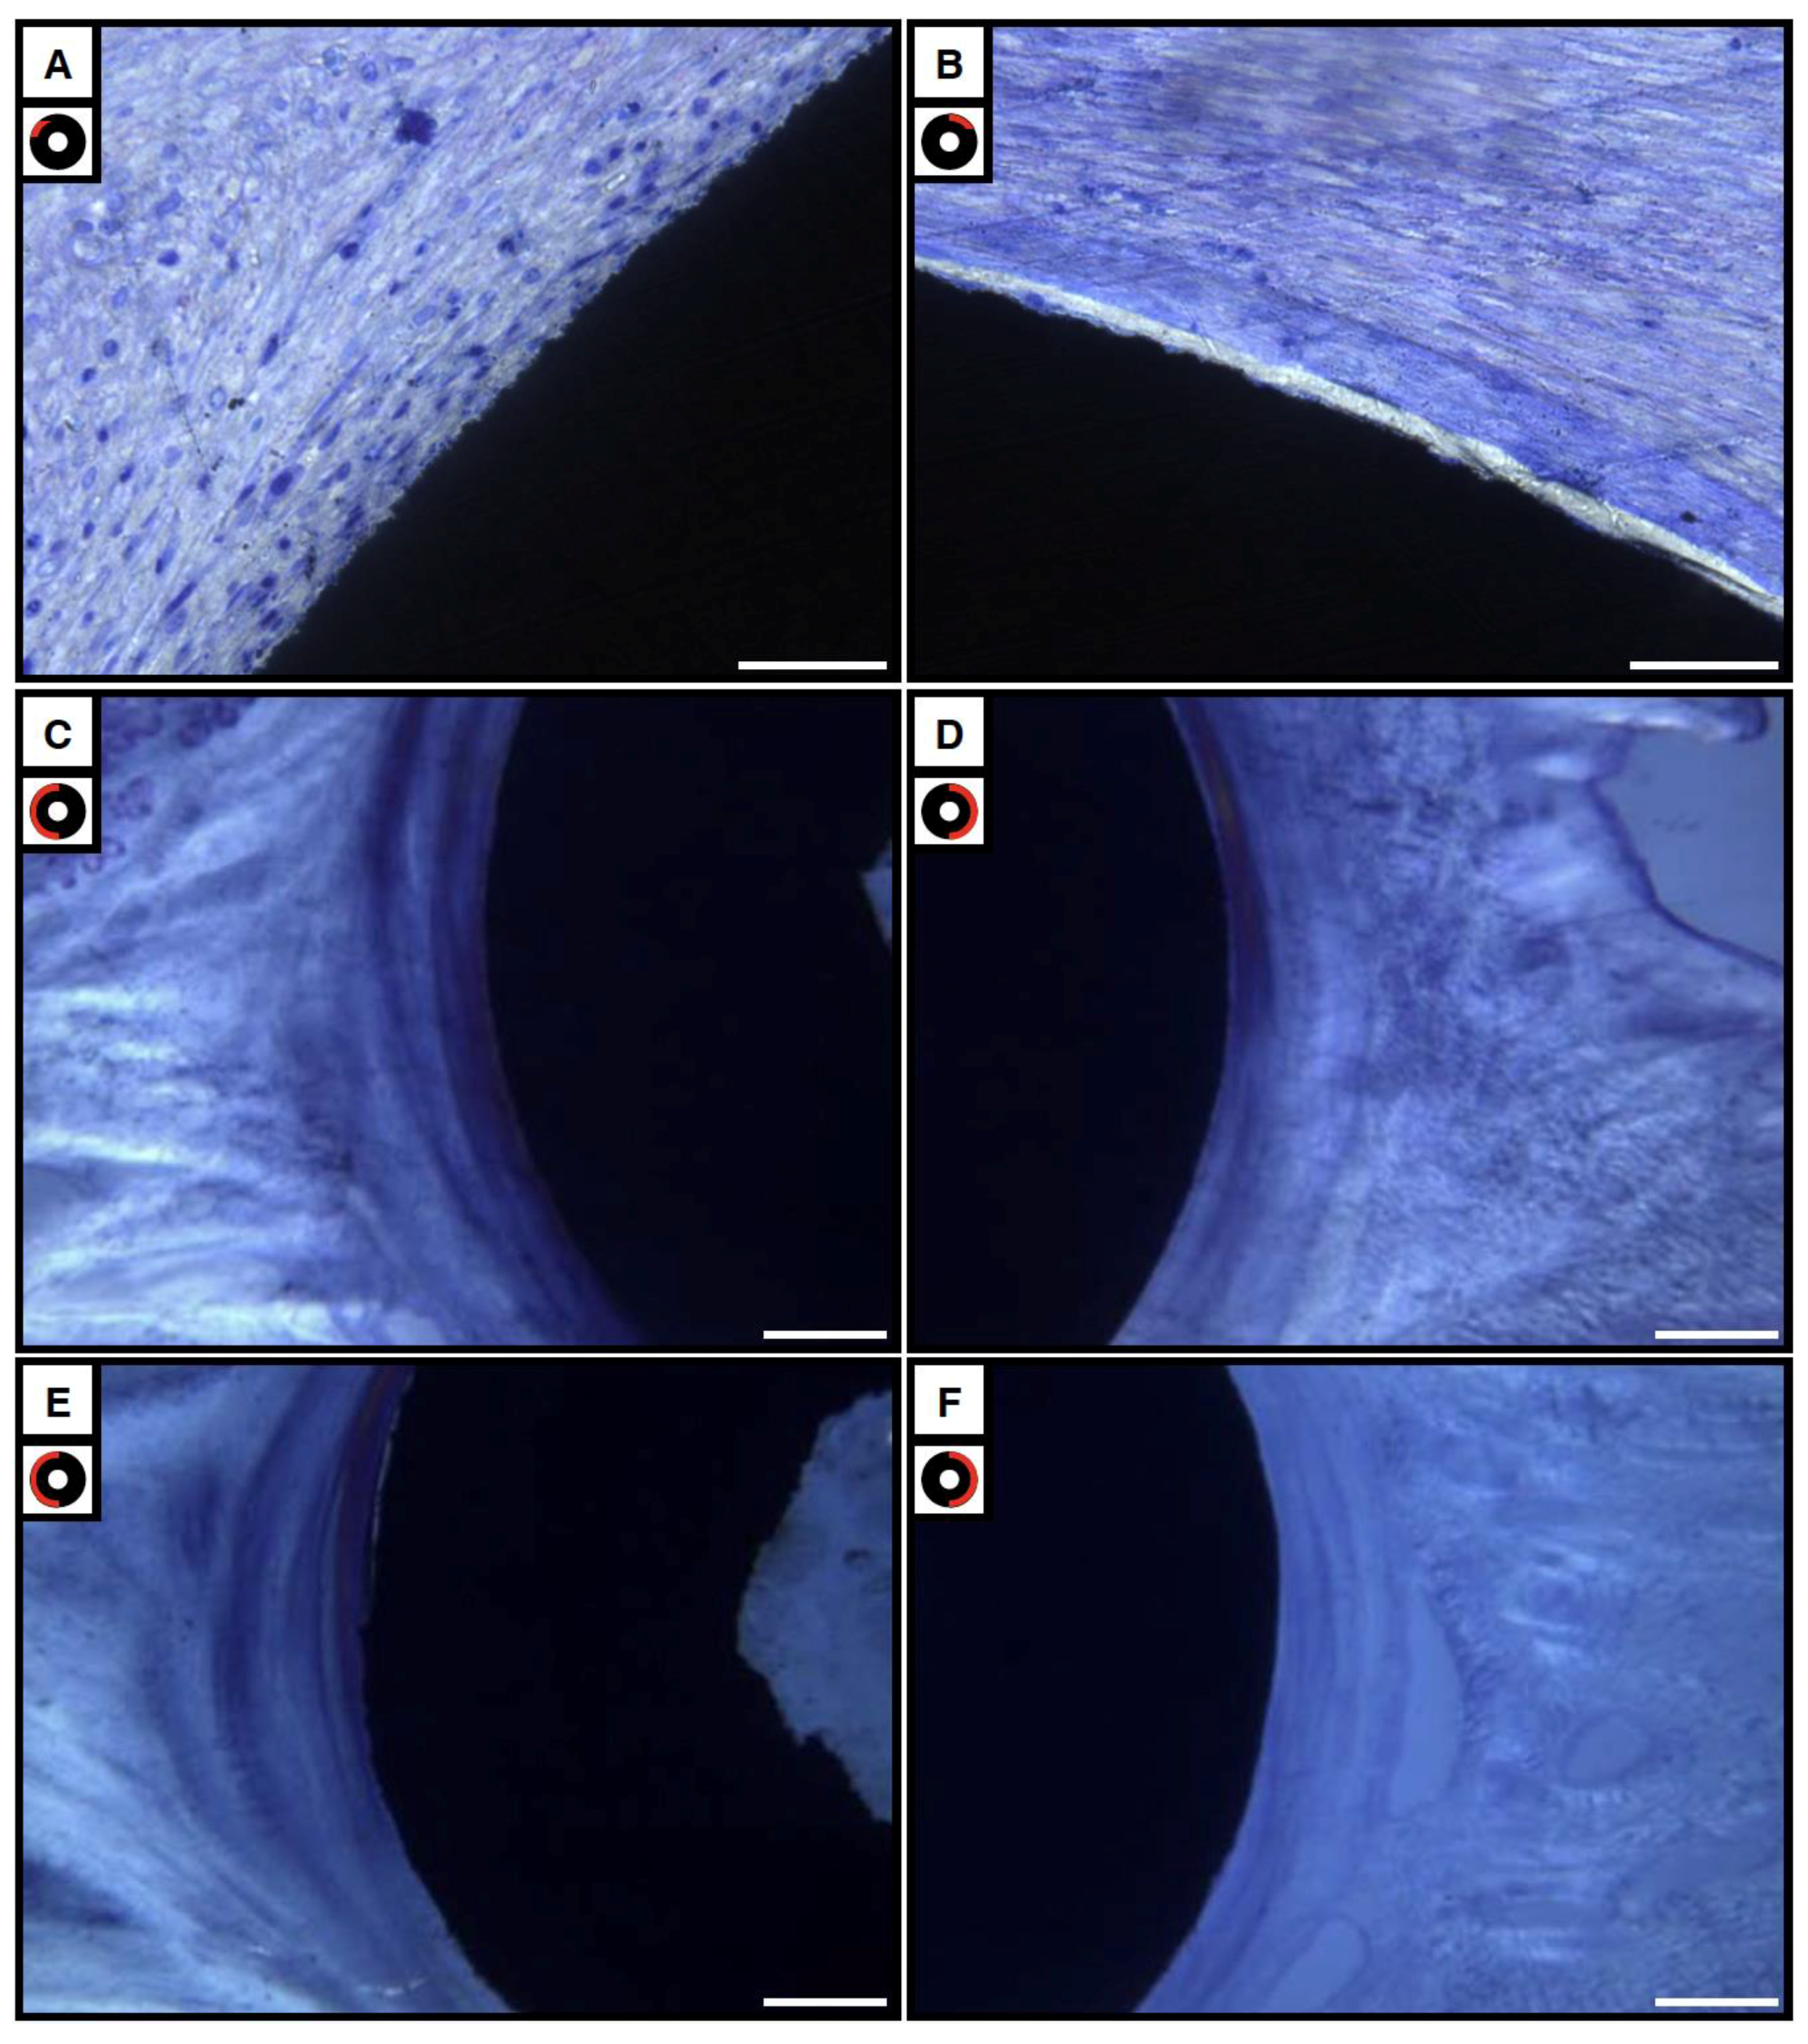

3.4.1. Bright and Polarized Light Microscopy

3.4.2. Scanning Electron Microscopy Observations